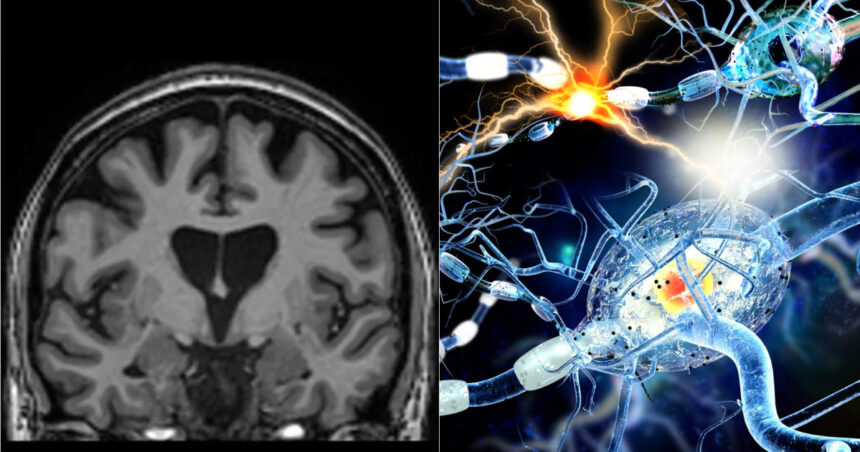

Una dintre cele mai devastatoare boli ereditare, boala Huntington, a fost tratată cu succes pentru prima dată, conform cercetătorilor de la UniQure, o companie de biotehnologie din Amsterdam. Studiul a evidențiat o încetinire cu 75% a evoluției bolii la pacienții care au primit noul tratament bazat pe o tehnică genetică inovativă.

Noul tratament implică utilizarea unui tip de material genetic numit micro-ARN, care oprește producerea proteinei responsabile pentru provocarea bolii. Boala Huntington este cauzată de o mutație genetică ce generează acumularea unei proteine numite huntingtin, care duce la distrugerea celulelor cerebrale.

Tratamentul necesită o intervenție chirurgicală delicată, care durează între 12 și 18 ore, și presupune introducerea în creier a unui virus modificat genetic. Acest virus acționează ca un „poștaș microscopic”, livrând secvența de ADN special concepută neuronilor, unde se activează pentru a produce molecula micro-ARN (AMT-130), menită să intercepteze instrucțiunile pentru producerea proteinei toxice.